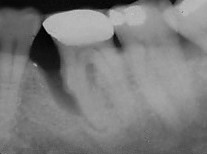

This is an example of an bone defect. The area was repaired and the xray on the bottom is a 23 year followup of a case we treated.

Before (1990)